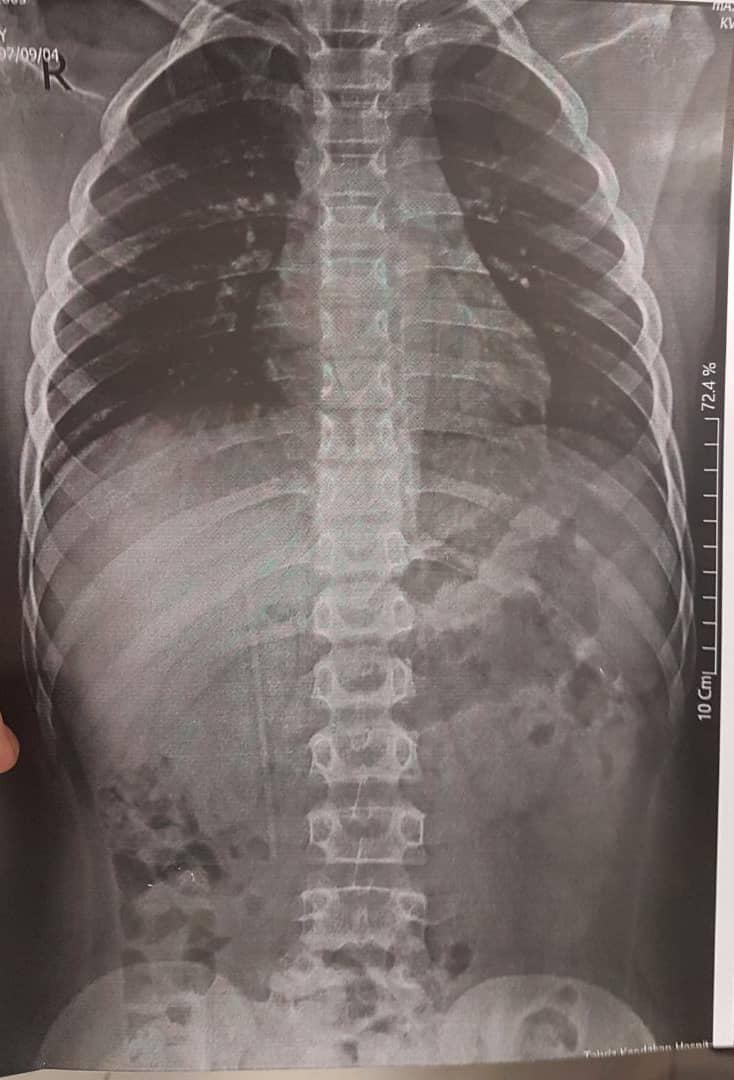

تصاویر مربوط به رادیوگرافی شکم و آندوسکپی کودک 9 ساله ای هست که بدنبال بلع مداد (2هفته قبل از مراجعه) توسط جراح محترم اطفال به بخش آندوسکپی بیمارستان امام رضا (ع) ارجاع داده شده بود.

درتصویر رادیوگرافی مشخص شد که مداد در ژژنوم قرار گرفته، بعد از انجام تمهیدات لازم کودک توسط دکتر مسعود شیرمحمدی از اساتید بخش گوارش تحت آندوسکپی  با آندوسکوپ بزرگسالان (با توجه به محل قرار گیری مداد در روده باریک) قرار گرفت که مداد با موفقیت و با استفاده از فورسپس جسم خارجی در آورده شد و کودک بدون مشکل خاصی از بخش آندوسکپی مرخص شد.